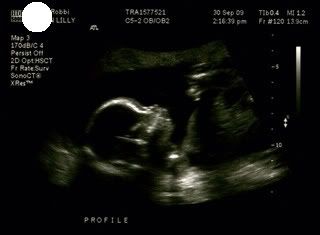

Ultrasound pictures 19weeks, 1 day (measured at 19weeks, 4 days - not too shabby for just relying on charting for my date).

Profile - arms crossed on chest: